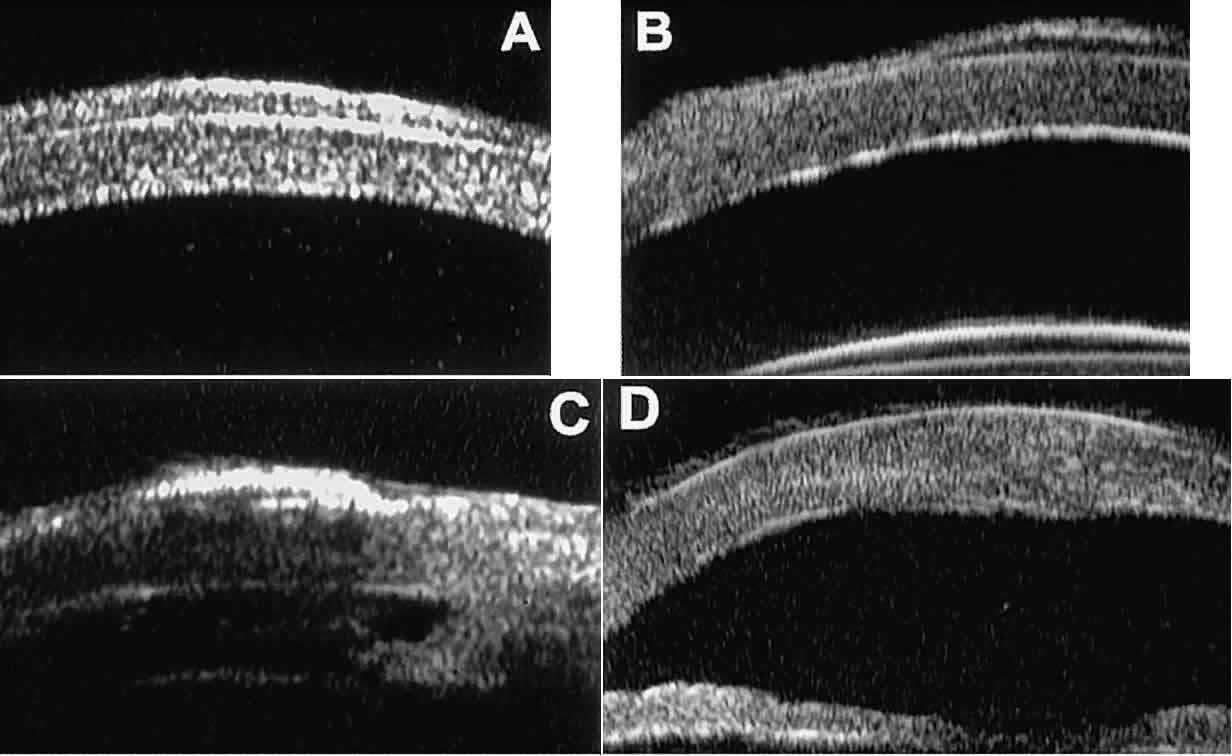

to evaluate the trabecular meshwork (Fig. 9).2,4 The angle configuration can be graded and compared with gonioscopic findings. In

certain patients with open-angle glaucoma, UBM can provide

information that may be of some diagnostic value (Fig. 10). For example, in pigment dispersion syndrome (see Fig. 10A),6 UBM typically reveals posterior bowing of the peripheral iris (“q” configuration

of peripheral iris by Spaeth classification5). In plateau iris syndrome (see Fig. 10B),7 UBM usually reveals abnormally steep anterior angulation of the peripheral

iris (“s”configuration of peripheral iris by Spaeth classification5), insertion of the iris from the anterior ciliary body, and retroiridic

projection of the ciliary processes. In eyes with peripheral anterior

synechiae (see Fig. 10C and D), UBM can reveal the extent of iridocorneal adhesion even if the cornea

is hazy or opaque.  Fig. 9. Angle configuration in eyes with open-angle glaucoma. A. Wide open angle with flat iris plane (D40r configuration by Spaeth gonioscopic

grading system). B. Moderately wide angle with anteriorly bowed iris plane (C30r by Spaeth

gonioscopic grading system). Fig. 9. Angle configuration in eyes with open-angle glaucoma. A. Wide open angle with flat iris plane (D40r configuration by Spaeth gonioscopic

grading system). B. Moderately wide angle with anteriorly bowed iris plane (C30r by Spaeth

gonioscopic grading system).

|

Fig. 10. UBM features of special glaucoma cases. A. Pigment dispersion syndrome with posterior bowing of peripheral iris (“q” configuration by Spaeth gonioscopic grading system). B. Plateau iris syndrome with origin of iris from anterior surface of ciliary

processes behind peripheral iris, slitlike narrowing of peripheral

angle, and abrupt transition from steep peripheral iris to flat iris

midzone. C. Broad peripheral anterior synechia with posterior bowing of nonadherent

iris. D. Peripheral anterior synechia with aqueous-filled slit between site of

iridocorneal adhesion and iris root after cataract extraction with implantation

of posterior-chamber IOL. Fig. 10. UBM features of special glaucoma cases. A. Pigment dispersion syndrome with posterior bowing of peripheral iris (“q” configuration by Spaeth gonioscopic grading system). B. Plateau iris syndrome with origin of iris from anterior surface of ciliary

processes behind peripheral iris, slitlike narrowing of peripheral

angle, and abrupt transition from steep peripheral iris to flat iris

midzone. C. Broad peripheral anterior synechia with posterior bowing of nonadherent

iris. D. Peripheral anterior synechia with aqueous-filled slit between site of

iridocorneal adhesion and iris root after cataract extraction with implantation

of posterior-chamber IOL.